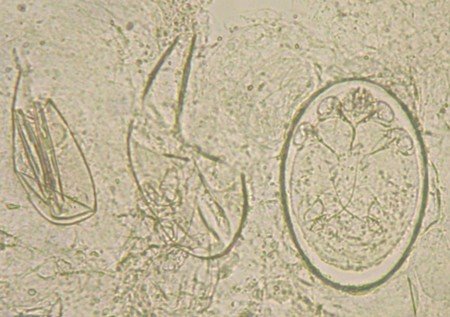

皮膚刮屑氫氧化鉀顯微鏡檢查,是診斷疥瘡的重要方法。以裸眼或放大鏡檢視,選取臨床上可疑的疥瘡病灶,以指縫、手腕或腋下之原發性隧道病灶或沒抓破的丘疹病灶為佳﹝老人可以選擇肩膀、背部或腹部病灶﹞,若病灶某一端有黑點,可能代表有疥蟲存在。以塗有薄層礦物油的解剖刀片,刮取病灶與周圍皮膚,刮取時最好刮到上部真皮,出現輕微點狀出血為佳,代表整層表皮已被完全刮下,吸附於刀片上。將刮下來的組織置於載玻片上,不加10% KOH﹝potassium hydroxide﹞,先在顯微鏡下尋找疥蟲的排泄物﹝scybala﹞;之後加入10% KOH,稍微隔火加熱促進反應後﹝可溶解皮膚角質與其他雜質﹞,在顯微鏡下尋找蟲體﹝圖七﹞、蟲卵﹝圖八﹞或蟲體斷肢。但在實際經驗中,皮膚刮屑氫氧化鉀顯微鏡檢查的敏感度﹝sensitivity﹞較低,因此即使沒有找到疥蟲相關證據,並無法排除疥瘡診斷的可能。

圖七 顯微鏡下的成年疥蟲(400X)。

圖八 顯微鏡下破掉的卵殼與卵中的幼蟲(400X)(劉勇佺醫師提供)。